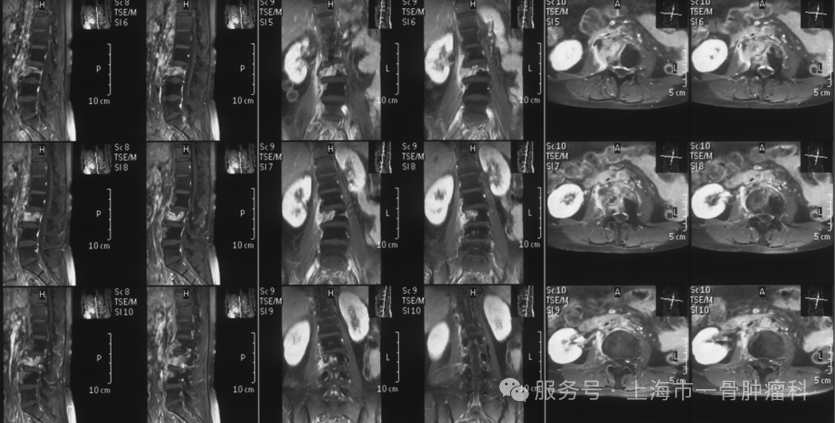

来自江苏的20岁小瑶同学,2022年12月因“腹部肿痛加重不适,无法下地行走”入院的。患者既往有脊柱侧弯手术病史